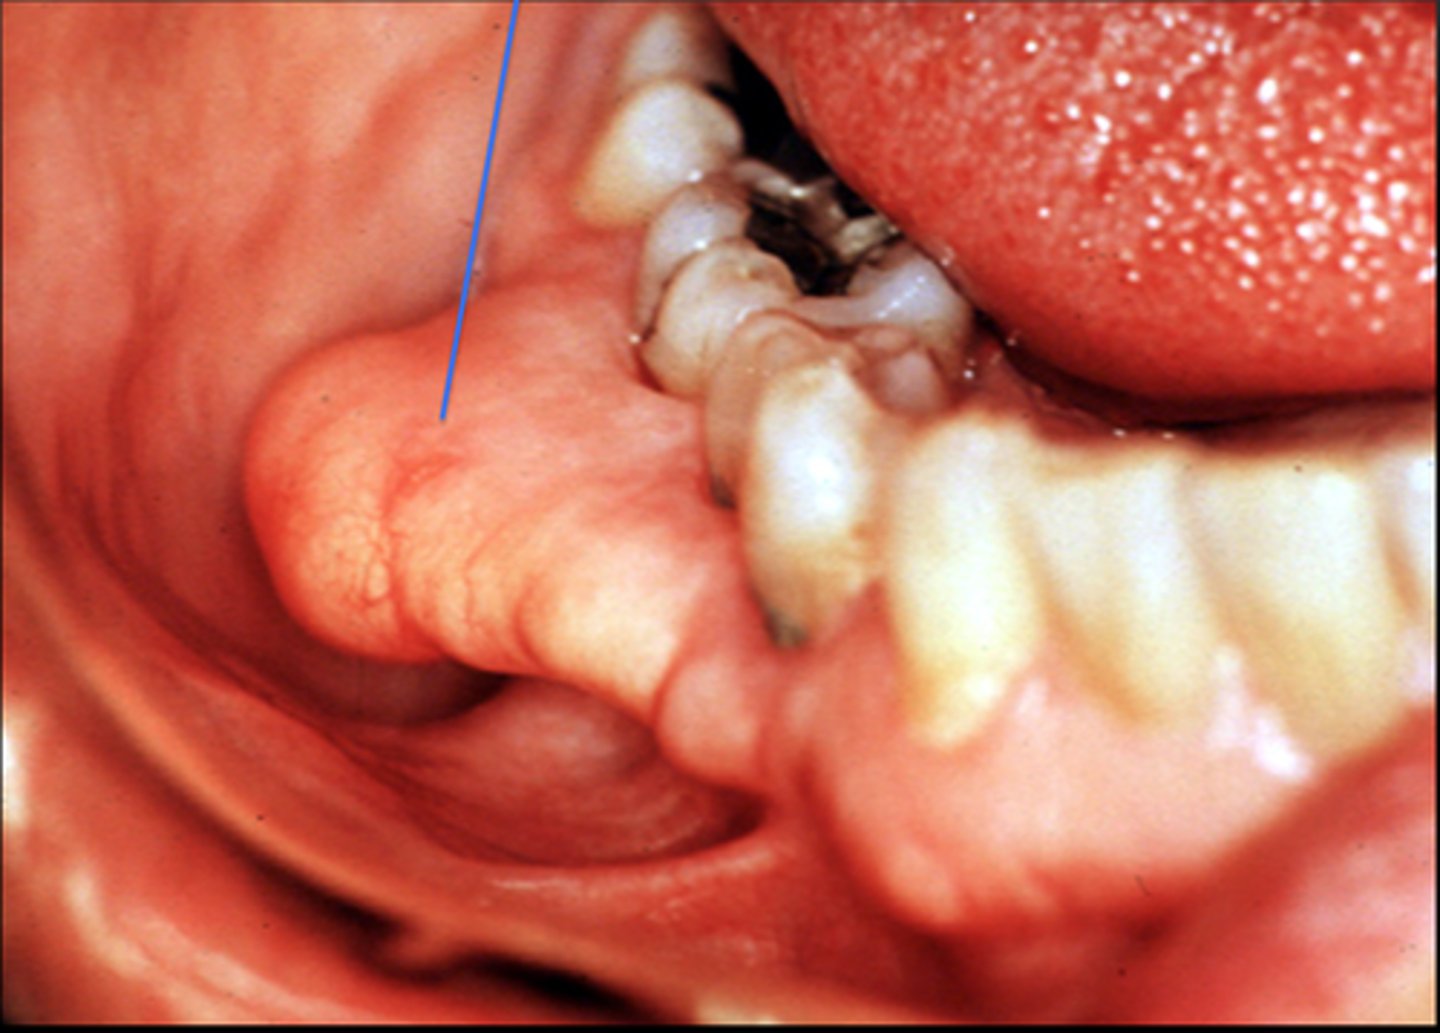

exostoses

slow grow

fine unless denture